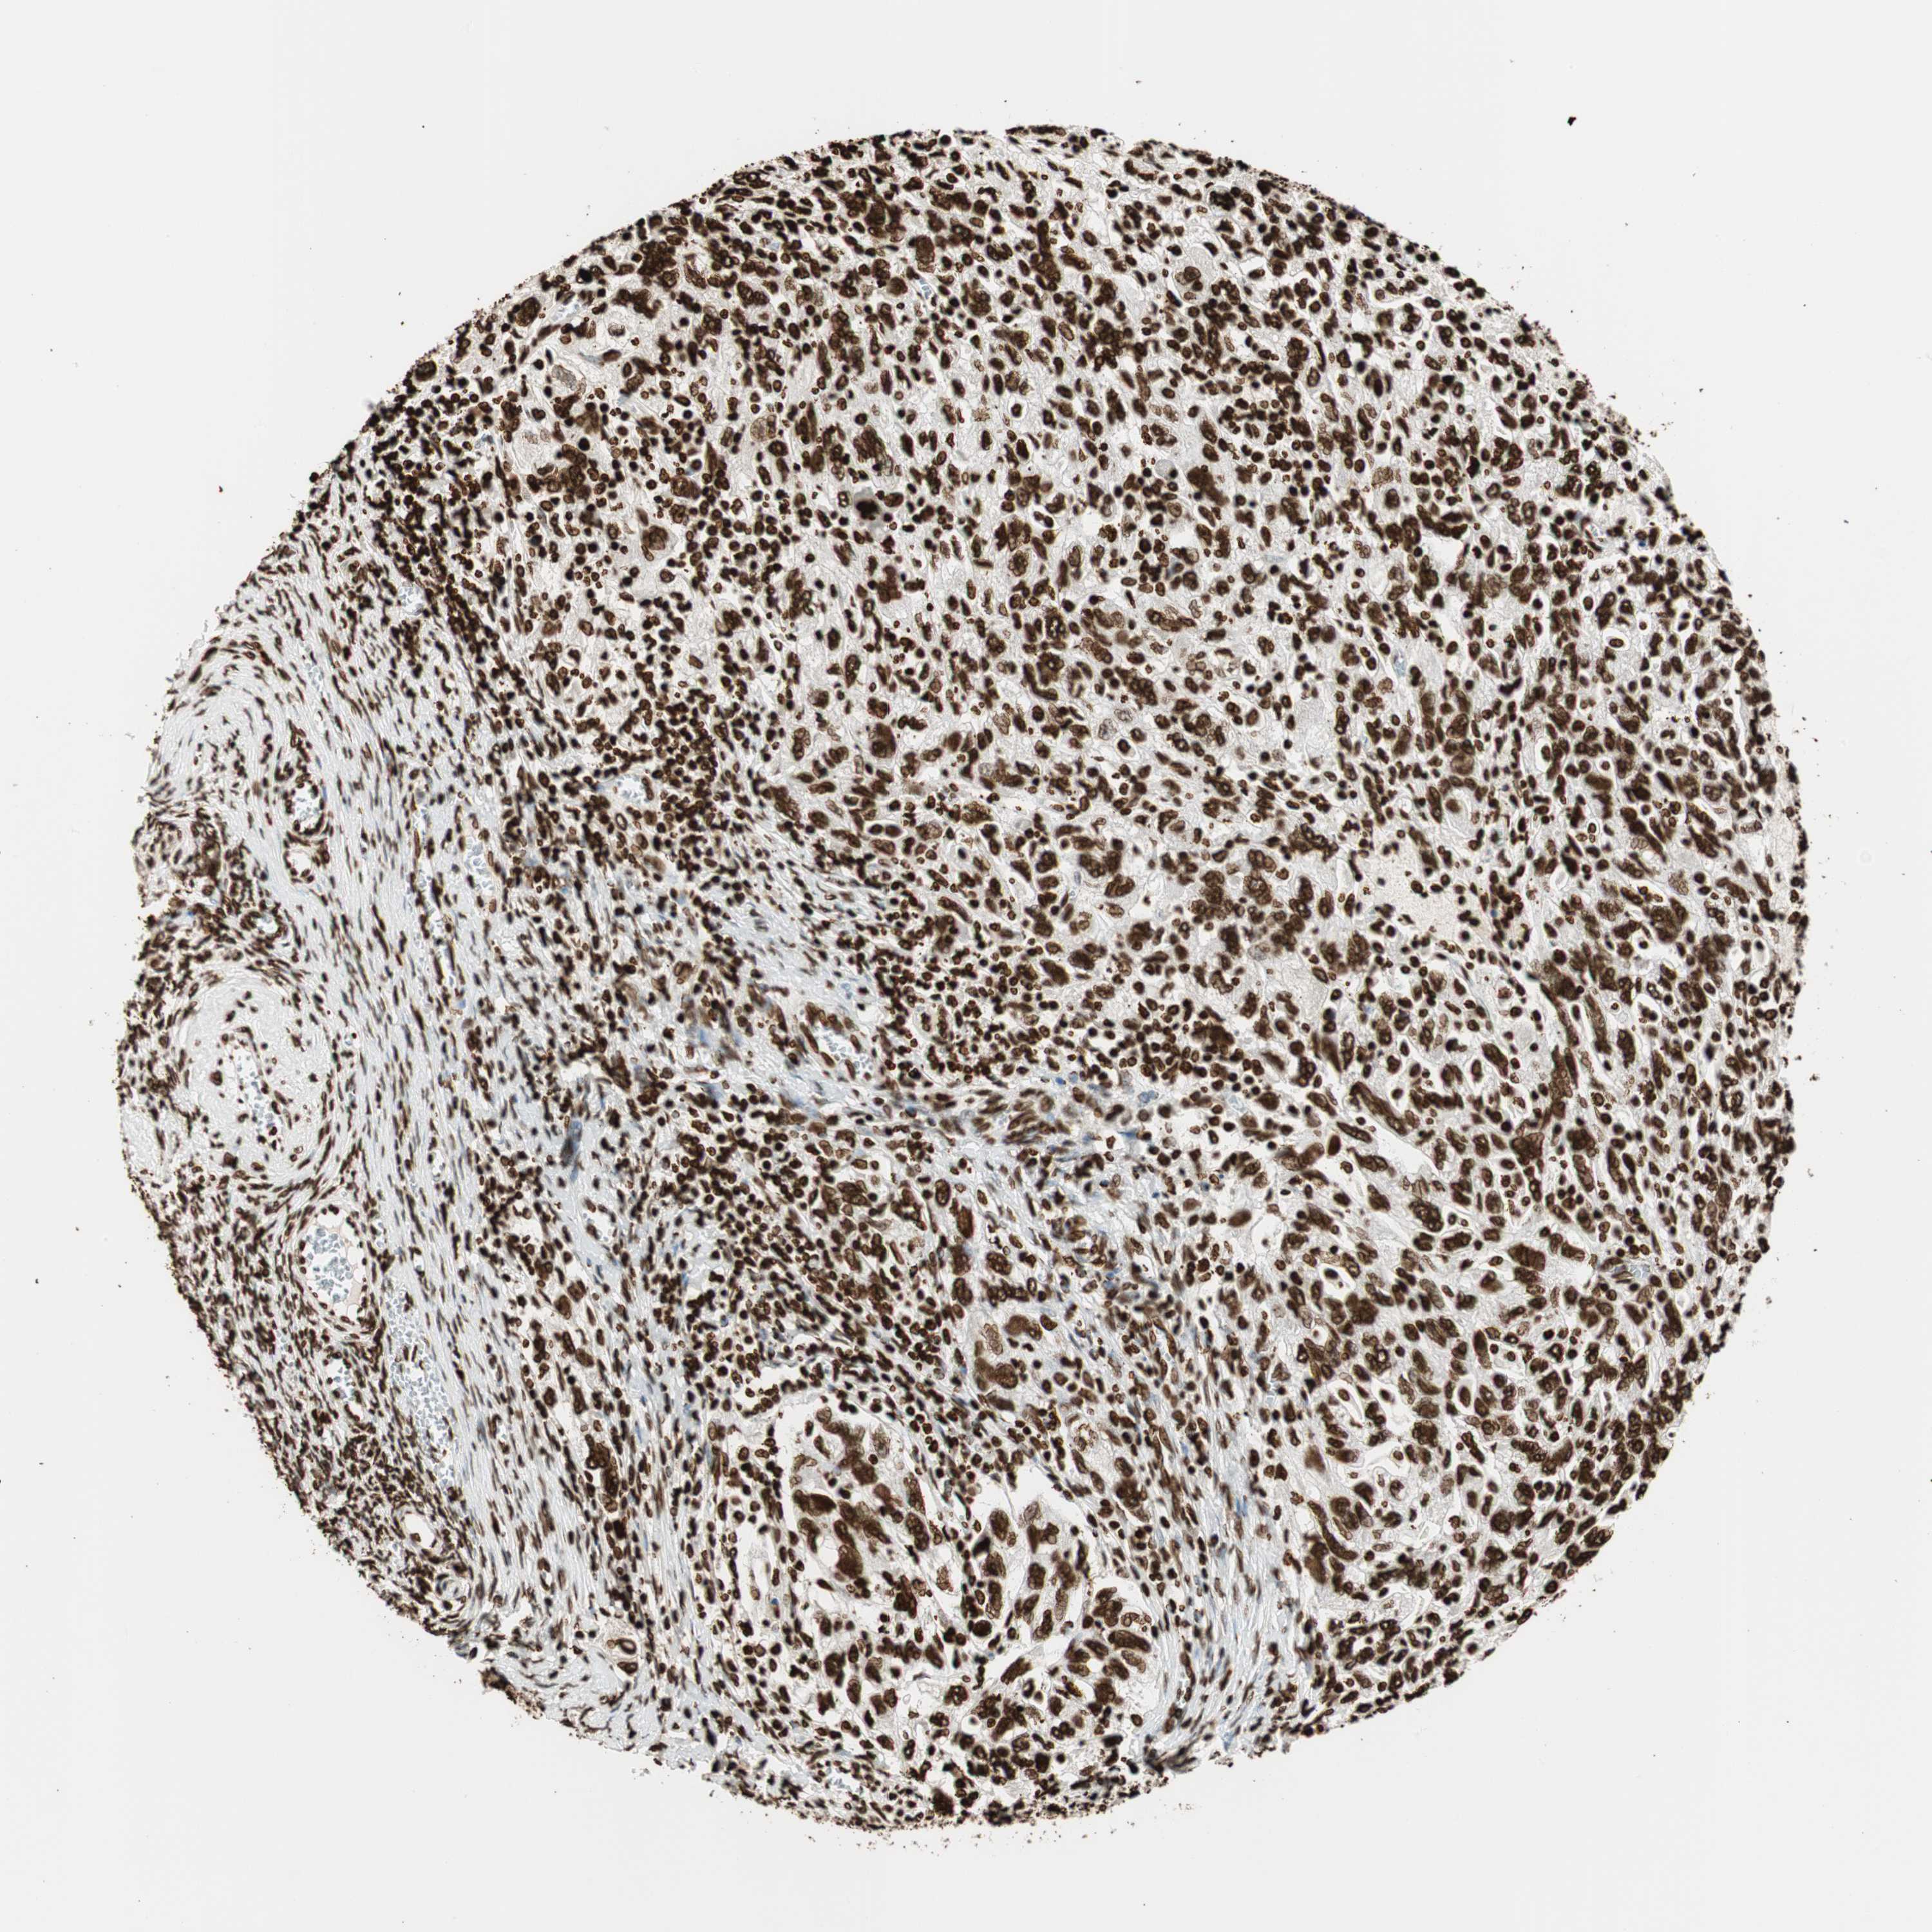

OVARIAN CANCER - Protein expressioni

A mouse-over function shows sample information and annotation data. Click on an image to view it in a full screen mode. Samples can be filtered based on level of antibody staining by selecting one or several of the following categories: high, medium, low and not detected. The assay and annotation is described here.

Note that samples used for immunohistochemistry by the Human Protein Atlas do not correspond to samples in the TCGA dataset.

Antibody stainingi

Antibody staining in the annotated cell types in the current human tissue is reported as not detected, low, medium, or high, based on conventional immunohistochemistry profiling in selected tissues. This score is based on the combination of the staining intensity and fraction of stained cells.

Each image is clickable and will lead to virtual microscopy that enables deeper exploration of all samples and also displays staining intensity scores, fraction scores and subcellular localization as well as patient and tissue information for each sample.

Antibody CAB008558

Staining

High

Medium

Low

Not detected

Intensity

Strong

Moderate

Weak

Negative

Quantity

>75%

75%-25%

<25%

None

Location

Nuclear

Cytoplasmic/membranous

Cytoplasmic/membranous,nuclear

Cystadenocarcinoma, serous, NOS

Carcinoma, endometroid

Cystadenocarcinoma, mucinous, NOS

Carcinoma, NOS